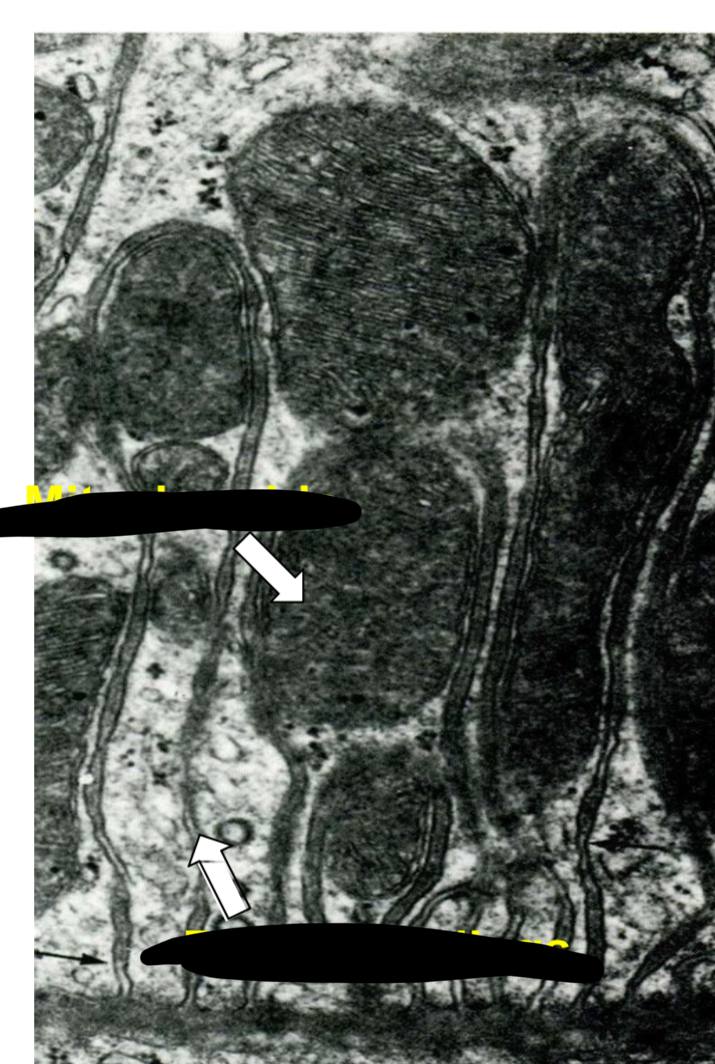

mitochondria

تشبه بصمه الاصابع والتعرجات اللي فيها نسميها cristae

basal infolding filled w mitochondrua